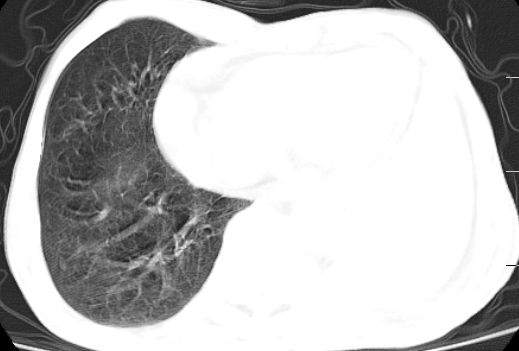

标题: CT10141:男、84岁,咳嗽、咯血1年。 [打印本页]

标题: CT10141:男、84岁,咳嗽、咯血1年。

支持左侧中央型肺癌伴下叶肺不张\\纵隔淋巴结转移.左侧包裹性胸腔积液\\心包积液.左侧少量胸腔积液..慢性支气管炎伴部分间质纤维化.

咯血病史较长,左肺下叶实变,体积未明显缩小,隐约可见血管影及坏死阴影,双肺门及纵隔淋巴结增大,心包增厚积液,纵隔右移位,单侧胸腔积液,首先考虑:大叶型肺泡癌伴纵隔心包转移。